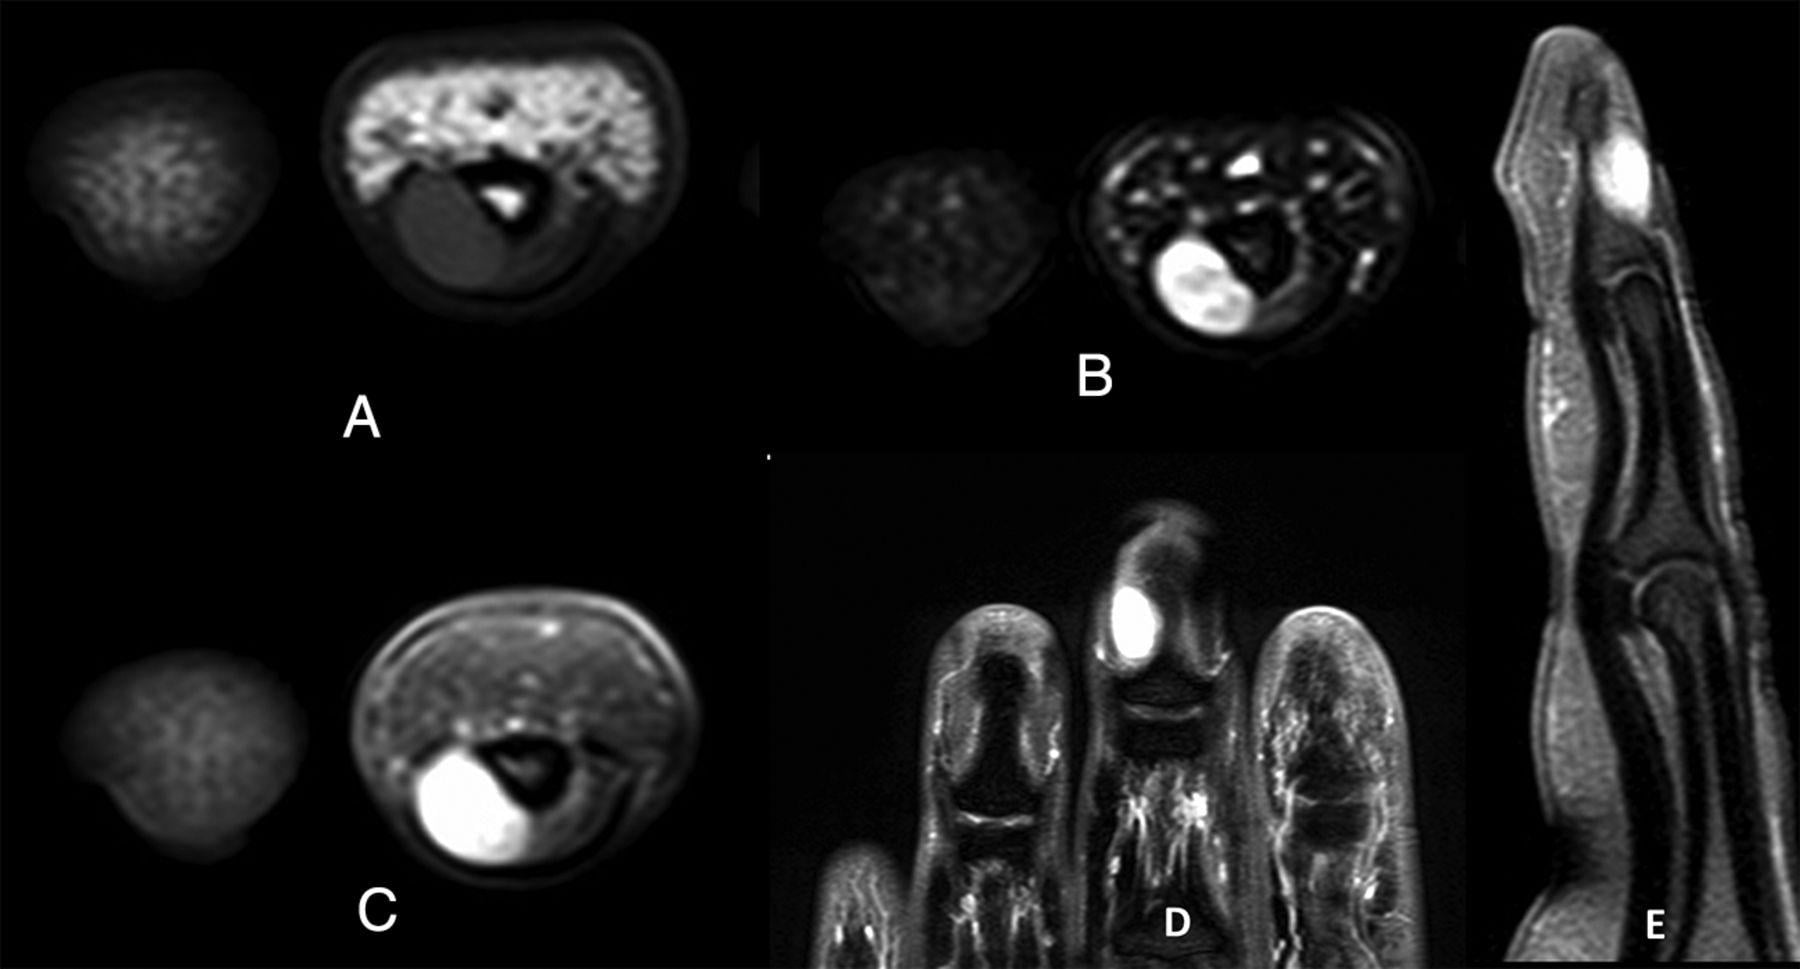

臨床上,甲床內的血管球瘤,在指甲下或呈紫藍色,但通常也難以察覺。倘若以筆尖擠壓患處,痛楚卻會一觸即發。因腫瘤對相連組織構成長期壓力,位於上方的指甲或已出現變形,而位於下方的指骨,在X光下亦會呈現被侵蝕的痕跡。然而磁力共振是最準確的診斷,可發現細至2毫米的血管球瘤。手術切除乃最佳的治療方案,一般可以在局部麻醉下透過顯微鏡徹底切除,術後不但與痛楚告別,再生的指甲亦不再變形。